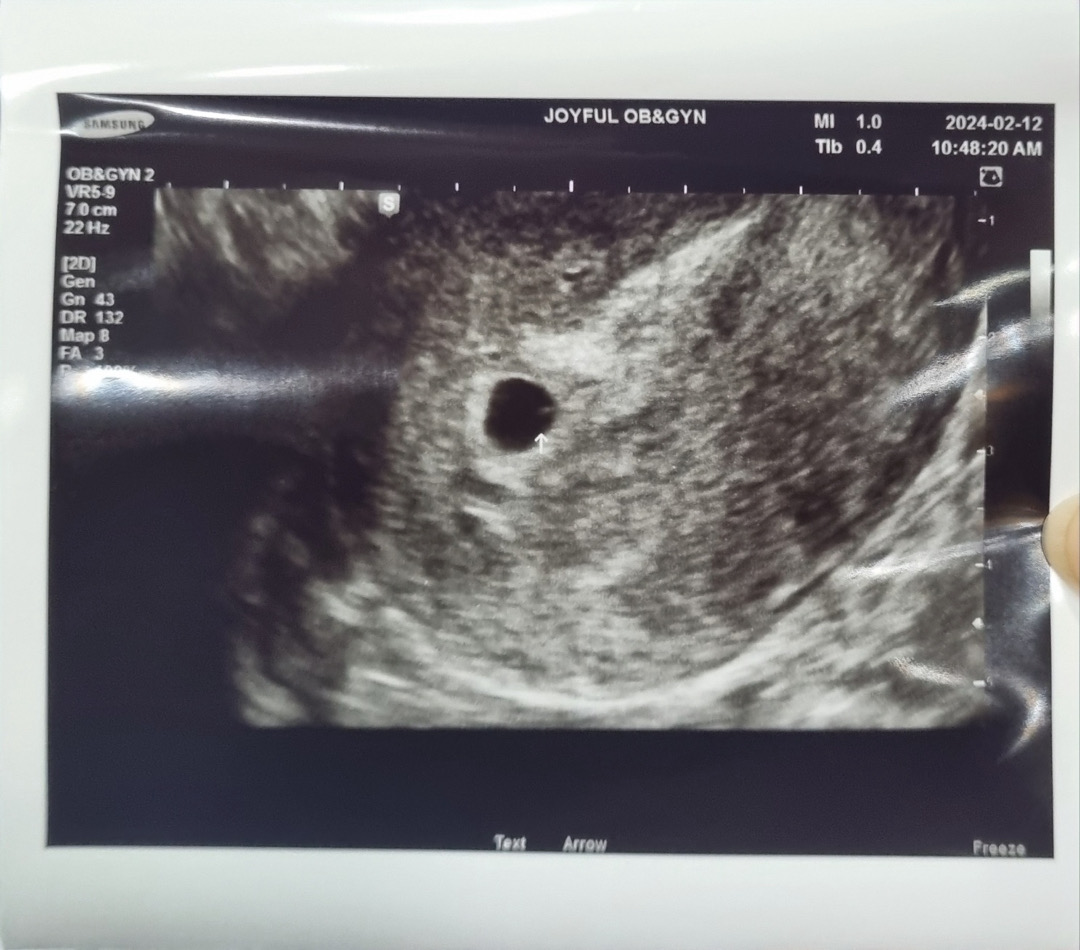

막생 1/1 배란추정일 1/19 2/5 피검 수치 130 2/12 아기집, 난황확인 5일에 피검하고 일주일 시간이 얼마나 안가던지ㅠㅠㅠ 드뎌 아기집하고 난황보고왔습니다! 막생기준으론 6주였는데 오늘 아기집 보시더니 5주 라고 하셨어요! 7mm 이라고 하신거같은데... 크기 괜찮은가요? 난황도 아직 좀 작다고 하시는데 괜찮은걸까요...?ㅠㅠ 다음엔 아기심소 들으러 갑니다...!!! 두근☺️